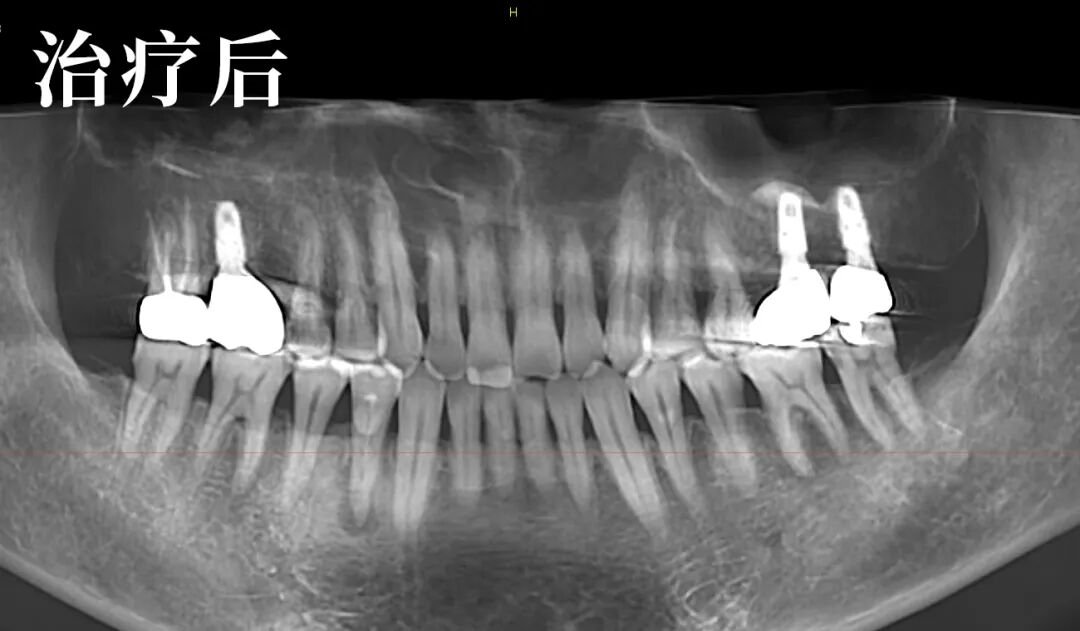

经过详细的检查及影像对比,朱医生发现了问题的特殊性:局部的炎症并非疼痛的主因,真正的问题在于患者自身双侧关节的先天不对称,导致了咬合力的异常分布。

这是一个典型的“继发性问题”——原有的修复体与患者独特的生理结构之间,产生了需要精细调整的力学冲突。

他邀请李先生一同观看影像,耐心解释道:“您看,问题的核心在于关节的先天条件导致了力量失衡。我们的目标不是简单地为你消炎,而是为您重建一个专属的、稳定的咬合平衡。”

这是一个为李先生量身定制的方案:待软组织充分恢复后,通过重新取模和精细的牙合调整,制作能适应其独特关节结构的新修复体。

治疗过程中,朱医生的操作稳健而轻柔。他不仅关注牙齿本身,甚至细致地观察到并引导纠正了患者长期形成的偏侧咀嚼习惯,从根源上巩固了治疗效果。